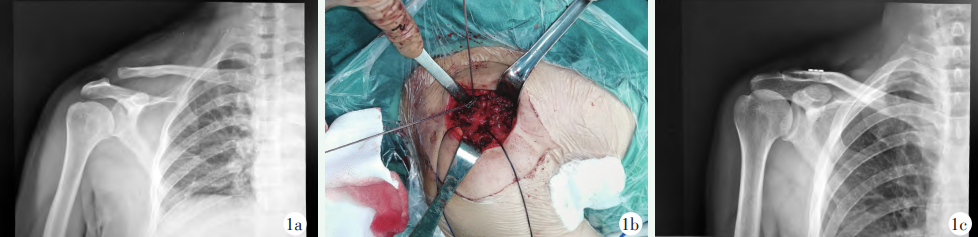

全身麻醉成功后,仰卧位。自喙突向肩锁关节做长约4cm的纵向切口,显露肩锁关节、锁骨远端和喙突基底,于锁骨中、前1/3距肩锁关节约3cm处向内外侧分别旁开约0.5cm使用2.5mm克氏针在锁骨上建立骨道,分别引入1号可吸收线作为牵引线备用。将袢钢板固定线和牵引线拆开备用。袢钢板牵引线绕过喙突基底,使用过线技术将双股固定线依次从锁骨内侧骨道、喙突基底、锁骨外侧骨道引出。固定线两端分别穿出条状袢钢板孔,复位肩锁关节,使用Nice结逐渐收紧,至肩锁关节略过度复位后打结固定(图1b)。于锁骨远端前外侧钻孔,引入1号可吸收缝线,向肩峰端后方的肩锁韧带和关节囊按“8”字缝合修复,冲洗切口,逐层缝合。术后X线片显示肩锁适当过度复位(图1c)。

图1 患者,男,46岁。1a:术前肩关节正位X线片示右侧肩锁关节Rockwood III型脱位;1b:术中固定线穿过袢板,分别预留修复喙锁韧带、肩锁韧带和关节囊的可吸收线;1c:术后正位X线片示肩锁关节适当过度复位。